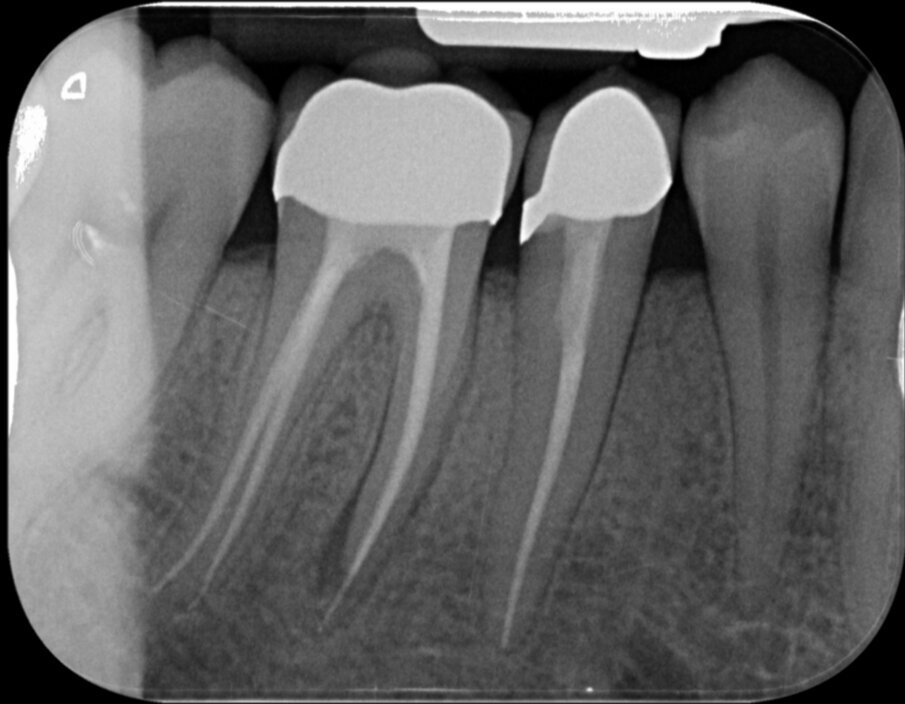

Mesiobuccaal en mesiolinguaal ontdoen we de kanalen van de Thermafil-carrier en de achtergebleven guttapercha. Een glijbaan hadden we vier jaar geleden ook, dus dit deel van de behandeling blijft redelijk eenvoudig. Het is vooral belangrijk geduldig te blijven en net zo lang de oplosmiddelen voor guttapercha in te laten werken en te activeren dat de paperpoints die we gebruiken om de oplosmiddelen weer op te deppen er brandschoon uitkomen (afbeelding 13). Deze keer geen Thermafil, maar de Squirt-techniek waarbij we guttapercha direct in de kanalen spuiten (afbeelding 14 en 15).

De eindfoto’s zijn duidelijk: een iets vollere shape en wat nadrukkelijkere puffs. Fingers crossed! Over drie maanden weten we meer.